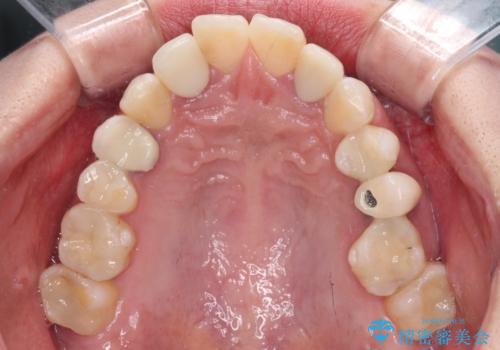

- クラウンから金属の土台が見えてきてしまったとのことで、作り替えを希望して来院された患者様です。

前歯や金属が露出している歯、痛みを感じる歯を中心に、オールセラミッククラウンにて補綴治療することとしました。

以前はセラミッククラウンのフレームとして金属が使用されており、歯肉の経年変化やセラミックのすり減りなどにより、金属が見えるようになってくることがあります。

現在は金属の代わりに強化セラミックを使用したオールセラミッククラウンが主流です。金属色が気になる方はご相談ください。